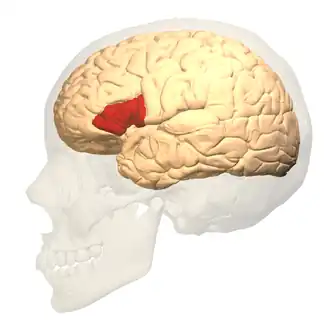

- Paul Broca identifies the speech production center of the brain.